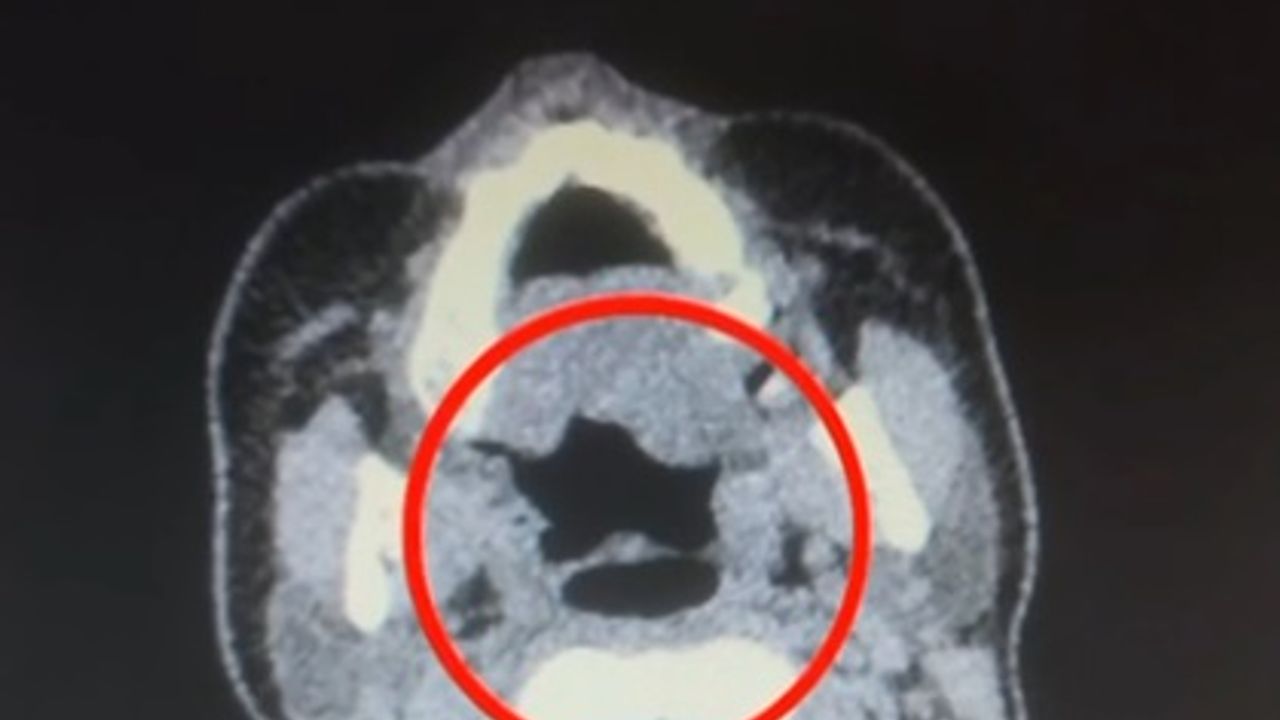

İl Emniyet Müdürlüğü Narkotik Suçlarla Mücadele Şube Müdürlüğü ekipleri, ‘Uluslararası uyuşturucu madde ticareti’ yapan kuryelerin yakalanmasına yönelik çalışma başlattı. Bu kapsamda düzenlenen operasyonda A.R. isimli kadın yakalandı. Gözaltına alınan şüpheli muayene için Kayseri Şehir Hastanesi'ne getirildi. Röntgen ve ultrasonda, A.R.’nin midesinde uyuşturucu madde olduğu tespit edildi. Şüphelinin midesinden kapsül halinde 500 gram metamfetamin, sağlık ekibinin müdahalesiyle çıkarıldı. Taburcu edilen şüpheli, polis merkezine götürüldü. (DHA)